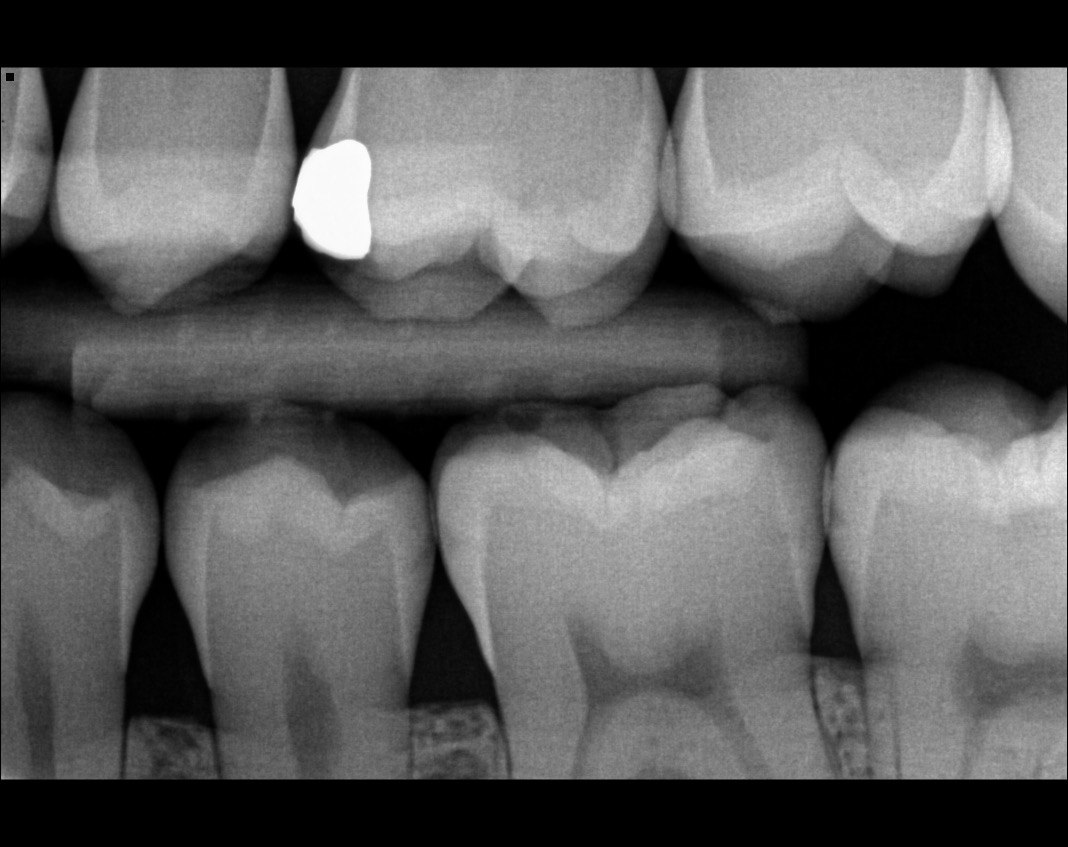

Question 1: What is the condition of the mesial surface of the tooth # 2.6?

Question 2. What is the condition of the mesial of the tooth # 2.7?

Question 3. What is the condition of the distal surface of the tooth # 2.7 and mesial surface of the tooth # 2.8 respectively?